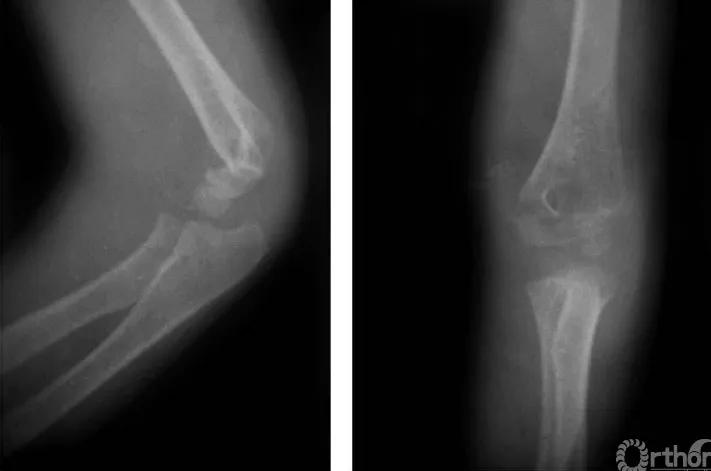

三、伸展型

例:肱骨下端骨骺分离伴前臂向后侧移位(图3)。

图3